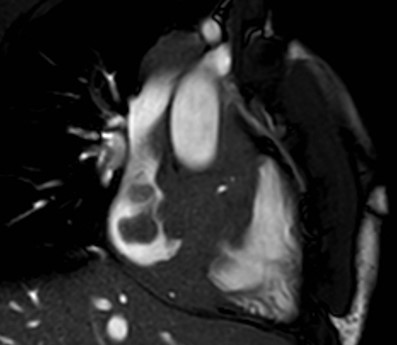

La risonanza magnetica (RM) cardiaca presentava nelle sequenze cine-SSFP (Steady State Free Precession) all’interno delle camere destre una massa ipointensa, infiltrante le pareti del miocardio, il pericardio, la valvola tricuspide, la radice aortica e la vena cava superiore (Figura 4).

linfoma_cardiaco_4.jpg

Figura 4

Infine, sulla base della RM cardiaca, la conferma dell’infiltrazione miocardica e pericardica, il rilievo della mancata infiltrazione dell'arteria coronaria destra e della scarsa vascolarizzazione, l’aspetto isointenso in T1, l’aspetto iperintenso in T2, e il lieve enhancement tardivo del gadolinio escludevano nuovamente la diagnosi di angiosarcoma, orientando al contrario verso quella di linfoma.